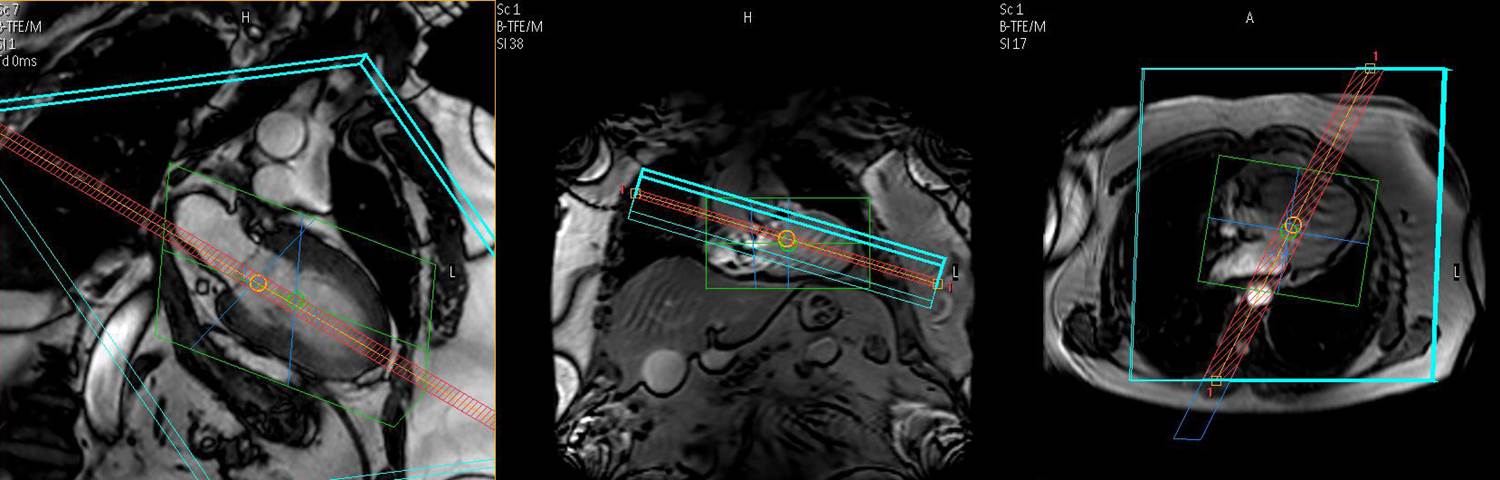

164. Frick M, Paetsch I, den Harder C, Kouwenhoven M, Heese H, Dries S, Schnackenburg B, de Kok W, Gebker R, Fleck E, Manka R, Jahnke C. Fully automatic geometry planning for cardiac MR imaging and reproducibility of functional cardiac parameters. J Magn Reson Imaging. 2011 Aug;34